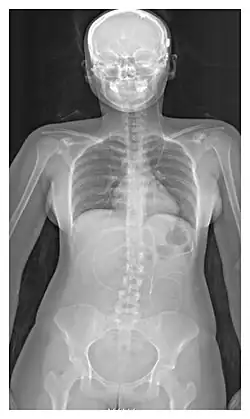

The location of the shunt is determined by the neurosurgeon based on the type and location of the blockage causing hydrocephalus. All brain ventricles are candidates for shunting. The catheter is most commonly placed in the abdomen but other locations include the heart and lungs.[11] Shunts can often be named after the route used by the neurosurgeon. The distal end of the catheter can be located in just about any tissue with enough epithelial cells to absorb the incoming CSF. Below are some common routing plans for cerebral shunts.

Ventriculo-peritoneal shunt (VP shunt) | Peritoneal cavity |

Ventriculo-atrial shunt (VA shunt) | Right atrium of the heart |

Ventriculo-pleural shunt (VPL shunt) | Pleural cavity |

Ventriculo-cisternal shunt (VC shunt) | Cisterna magna |

Ventriculo-subgaleal shunt (SG shunt) | Subgaleal space |

Lumbar-peritoneal shunt (LP shunt) | Peritoneal cavity |